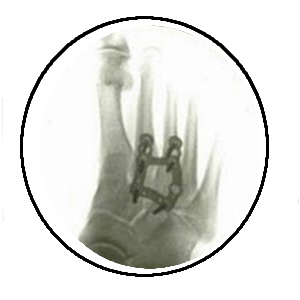

In November

2016, facing severe pain and an

inability to walk, Valerie underwent

foot surgery, where the surgeon was

taken aback by the condition of her

right foot. The procedure revealed

significant damage due to missing

cartilage, necessitating a joint fusion

of the top of her foot and two middle

toes using titanium steel, reflecting

the extent of her health decline

following the Levofloxacin treatment.